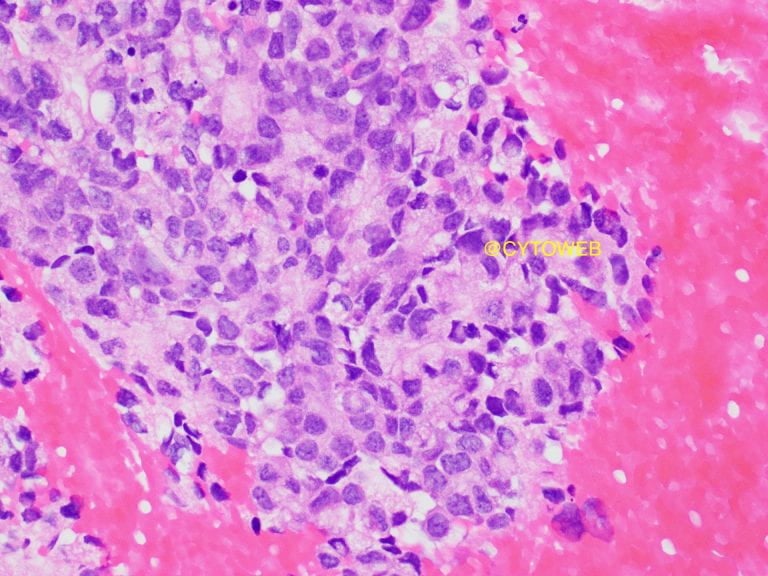

- Round to oval eccentric nuclei with mild nuclear pleomorphism

- Fine powdery chromatin and inconspicuous nucleoli

- Moderate to abundant pale cytoplasm

Commentary:

Provisionally, the diagnosis is metastatic adenocarcinoma. Given the clinical history of an elderly male, primary sites to consider include lung, upper gastrointestinal tract, pancreatobiliary system, lower gastrointestinal tract and prostate.

There are some morphologic clues to the site of origin, can you identify them?